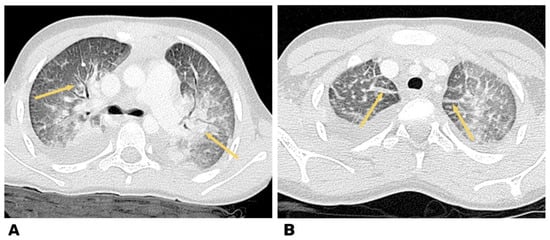

The data of the chest computed tomography (CT), including contrast agent for determination of vascular thrombosis, are shown in Figure 4.

Figure 4.

Heart CT angiography, axial plane, and pulmonary regimen in a 7-year-old child. (A) Reduction in lung pneumatization due to extensive confluent ground glass attenuation. (B) Free fluid was determined in the pleural cavities on both sides.

The CT and CT-angiography, a diffuse decrease of the lung pneumatization was diagnosed due to extensive confluent “ground-glass” attenuation, and free fluid up to 25 and 30 mm was determined in the pleural cavities on the right and left, respectively. The signs of left-sided thromboembolism of subsegmental branches of the A8 pulmonary artery and heterogeneity of pneumatization were diagnosed (Figure 4).